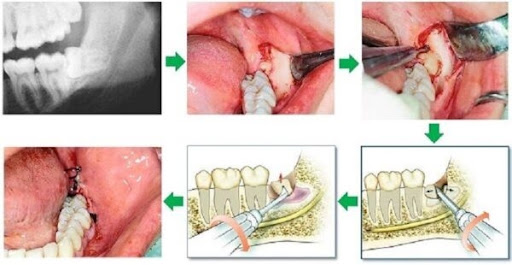

Hình ảnh sau khi nhổ răng khôn

Dưới đây là một số hình ảnh lỗ sau khi nhổ răng khôn của bạn tại Nha Khoa Miền Tây: